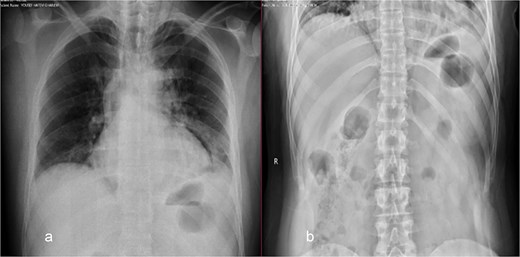

On examination, the patient was vitally stable and not in respiratory distress. His abdomen revealed epigastric tenderness with guarding, with no other significant systemic findings. Abdominal X-ray was normal (Fig. 1). Chest X-ray showed perihilar infiltration and right bronchus bulge (Fig. 1), raising suspicion for aspiration or other pathology. Given the findings, both medical and surgical teams were consulted. A chest and abdominal CT scan with contrast was recommended for further evaluation. However, the family refused and opted for gastroscopy only, despite being informed about the risks.

Chest (a) and standing abdomen (b) X-ray: Showed wide mediastinum with pneumomediastinum more at left side and right bronchus bulge. Normal standing abdomen X-ray.